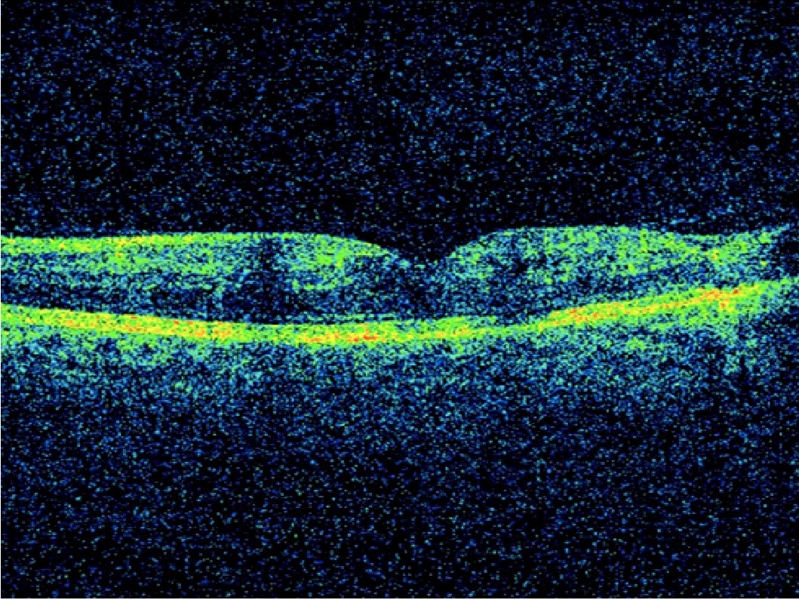

En las Figuras 6 a 9 se muestra un paciente con oclusión de vena central de la retina en el ojo izquierdo en el momento del diagnóstico (

Figura 6). En la imagen de OCT (

Figura 7) se aprecia edema macular cistoideo asociado a desprendimiento de la retina neurosensorial. Finalizado el tratamiento con tres dosis de antiangiogénicos separadas 1 mes, se observa una mejora en el aspecto fundoscópico (

Figura 8), con resolución parcial de las hemorragias retinianas, pero en la imagen de OCT (

Figura 9) se observa que no se ha detectado mejora anatómica, sino que hay un aumento del fluido subretiniano.

Figuras 6 y 7. Oclusión de la vena central de la retina del ojo izquierdo isquémica antes del tratamiento. Figura 6: Retinografía. Figura 7: OCT que muestra edema macular cistoideo con desprendimiento de la retina neurosensorial.

Figuras 8 y 9. Oclusión de la vena central de la retina del paciente de las Figuras 6 y 7 tras el tratamiento con antiangiogénicos (tres dosis en 3 meses consecutivos). En la retinografía (Figura 8) puede apreciarse la disminución notable del número de hemorragias. En la imagen de OCT (Figura 9) se observa la persistencia del engrosamiento retiniano con quistes intraretinianos, pérdida del contorno foveal y desprendimiento de la retina neurosensorial.